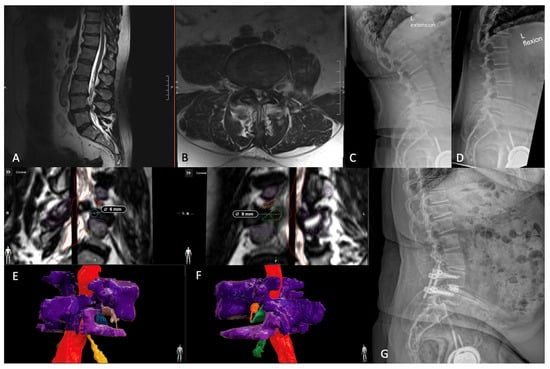

- Tabarestani, T.Q.; Salven, D.S.; Sykes, D.A.W.; Bardeesi, A.M.; Bartlett, A.M.; Wang, T.Y.; Paturu, M.R.; Dibble, C.F.; Shaffrey, C.I.; Ray, W.Z.; et al. Using Novel Segmentation Technology to Define Safe Corridors for Minimally Invasive Posterior Lumbar Interbody Fusion. Oper. Neurosurg. 2023. [Google Scholar] [CrossRef] [PubMed]

- Tabarestani, T.Q.; Sykes, D.A.W.; Kouam, R.W.; Salven, D.S.; Wang, T.Y.; Mehta, V.A.; Shaffrey, C.I.; Wiggins, W.F.; Chi, J.H.; Abd-El-Barr, M.M. Novel Approach to Percutaneous Lumbar Surgeries via Kambin’s Triangle-Radiographic and Surgical Planning Analysis with Nerve Segmentation Technology. World Neurosurg. 2023, 177, e385–e396. [Google Scholar] [CrossRef] [PubMed]

- Tabarestani, T.Q.; Sykes, D.A.W.; Maquoit, G.; Wang, T.Y.; Ayoub, C.M.; Shaffrey, C.I.; Wiggins, W.F.; Abd-El-Barr, M.M. Novel Merging of CT and MRI to Allow for Safe Navigation into Kambin’s Triangle for Percutaneous Lumbar Interbody Fusion-Initial Case Series Investigating Safety and Efficacy. Oper. Neurosurg. 2023, 24, 331–340. [Google Scholar] [CrossRef] [PubMed]